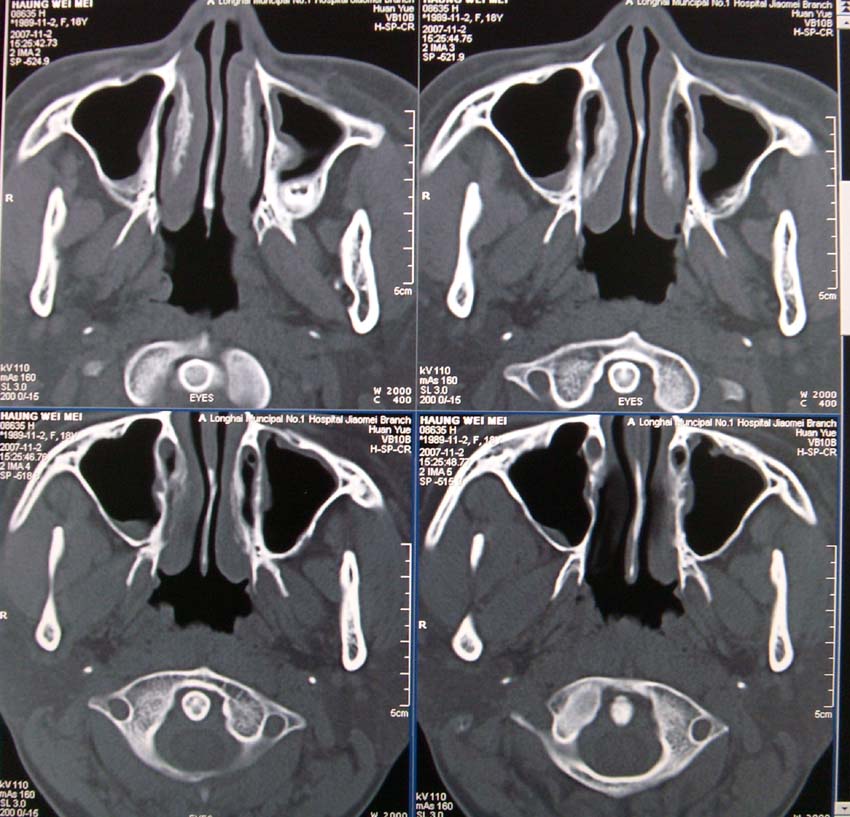

请问左侧上颌窦内见牙根影,是正常吗。

两侧上颌窦粘膜增厚,为慢性炎症;余为正常表现。

两侧上颌窦粘膜增厚,为慢性炎症;牙根影正常

双上颌窦炎症,余未见异常.冠状位重建,有助了解牙根的解剖位置.

两侧上颌窦粘膜增厚,为慢性炎症;牙根影正常.鼻甲粘膜肥厚.